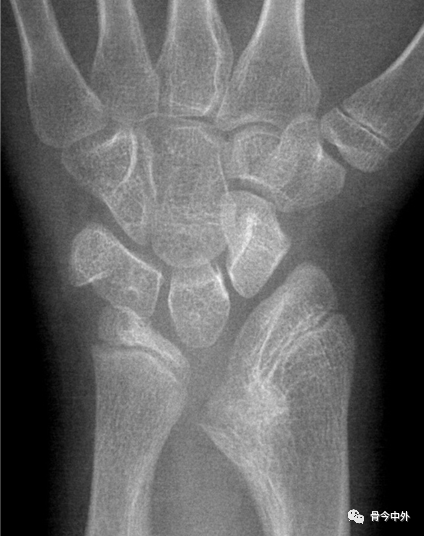

图7 a.舟骨、月骨切线;b. 月骨三角骨切线;c.尺骨远端关节面切线;d.腕骨总高度;e.头状骨长度。A.腕骨角;B.尺腕角 。

A.约130°。腕关节骨折、脱位时此角增大,此角减小见于Madelung畸形和卵巢发育不全。

B.正常为21~51˚。若此角度改变,提示腕骨骨折或腕关节脱位。

*腕骨高度指数:d与第3掌骨长度的比值,正常范围0.54±0.03。Nattrass腕骨高度指数为d/e,正常范围1.57±0.05。在月骨缺血坏死、不稳定型舟骨骨不连、腕关节不稳时,腕骨高度指数减小。